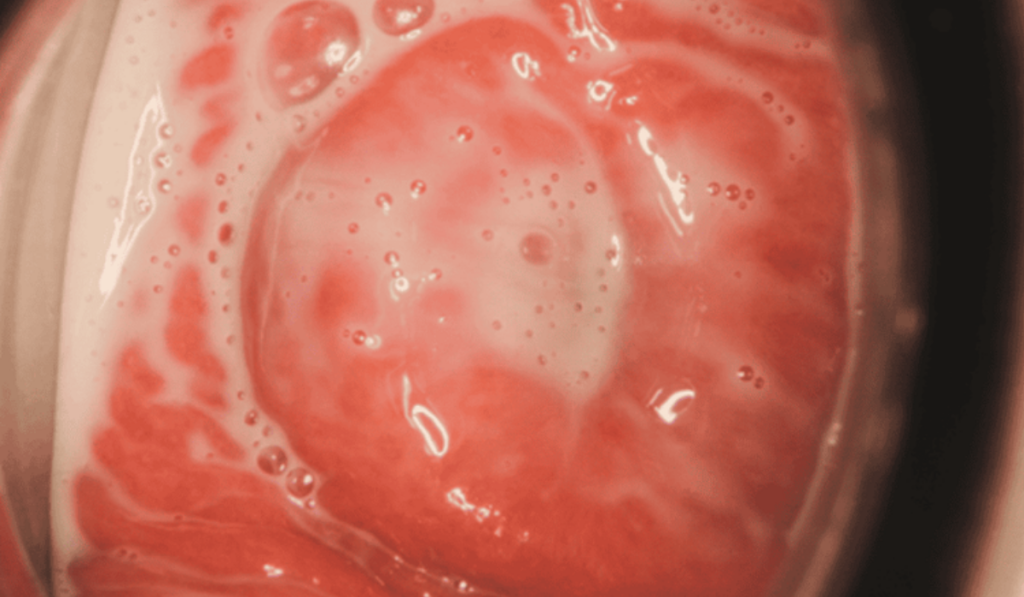

2. Hình ảnh ngứa do viêm âm đạo do vi khuẩn (Bacterial Vaginosis)

- Mô tả hình ảnh: Vùng kín thường xuyên trong tình trạng ẩm ướt, niêm mạc có màu hồng nhạt hoặc xám nhẹ.

- Dấu hiệu nhận diện: Dịch tiết loãng, có màu trắng xám. Đặc biệt, mùi hôi tanh như cá thối tỏa ra rất rõ rệt sau khi quan hệ hoặc trong kỳ hành kinh.